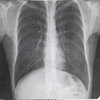

collapsing lung

dust clogged airways

albuterol induced stupidity